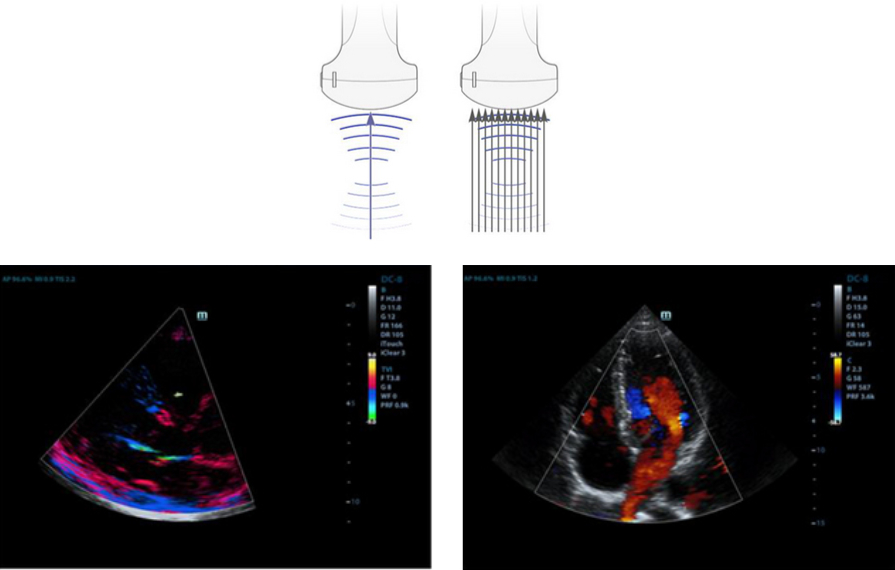

Forma??o de feixe enriquecido por eco

O formador de feixe enriquecido por eco permite o uso de sinais de eco tradicionalmente negligenciados de feixes adjacentes para formar um feixe de imagem mais fino e mais forte, proporcionando uma melhor resolu??o de imagem "fora de foco" e uma penetra??o mais profunda de imagem.

Forma??o de feixes m├║ltiplos

M├Īximo de 12 vezes de tarefa para um feixe transmitido, resultando em resolu??o de tempo excelente e maior taxa de quadros.